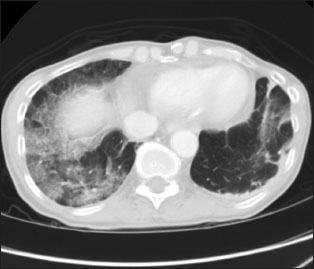

Chest computed tomography [Figure 5]{Figure 5}

| Figure.5:Computed tomography scan of a case of incidentally detected coronavirus disease 2019. Known case of lung malignancy underwent upper abdominal computed tomography for staging workup. Computed tomography sections in the lung window through lung bases show focal ground peripheral glass densities bilaterally, right more than left

-

New multifocal, peripheral, subpleural, and bilateral ground-glass opacities

Subpleural sparing may be present

Ground-glass opacities can be rounded or not sharply demarcated.